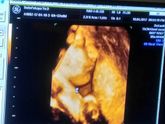

Давно ничего не писала, захотелось поделиться мыслями. Узи уже все прошла, на последнем (в 32 недели) вес был 1836г. Делала в Центре Медицины Плода, 3Д. Пинается моя малышка постоянно справа, особенно когда сижу или лежу на боку.